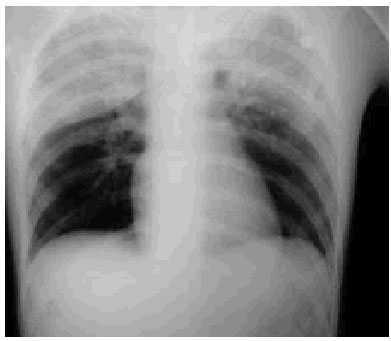

Se le realizó un estudio radiográfico torácico donde se observaba una imagen de densidad homogénea extensa que afectaba al lóbulo pulmonar superior derecho, limitado por la cisura menor; asimismo, presentaba un infiltrado de características alveolares segmentarias en el lóbulo superior izquierdo. No se visualizaron fracturas costales, neumotórax ni hemotórax. A la radiografía de pelvis se observó una fractura en la pala ilíaca izquierda.